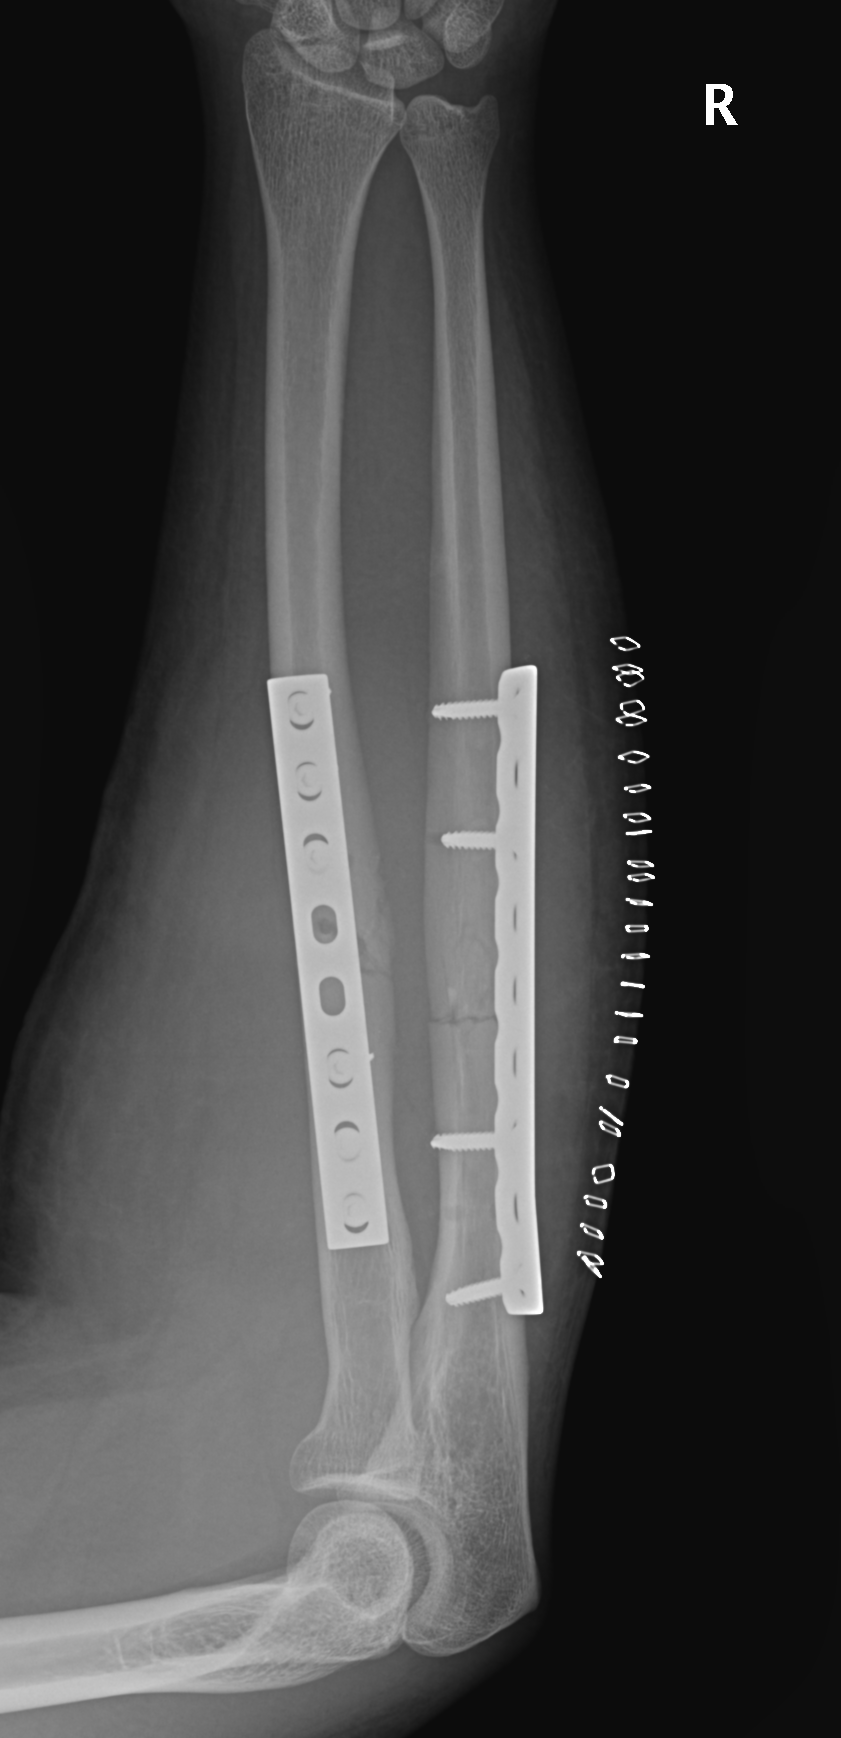

Masquelet induced membrane technique - defects up to 5 cm

Vascularized fibular bone graft - defects > 5 cm

Masquelet

- 32 infected forearm nonunions

- first stage: removal hardware / antibiotic cement for 6 weeks

- second stage: cancellous bone graft + plate

- 100% union rate